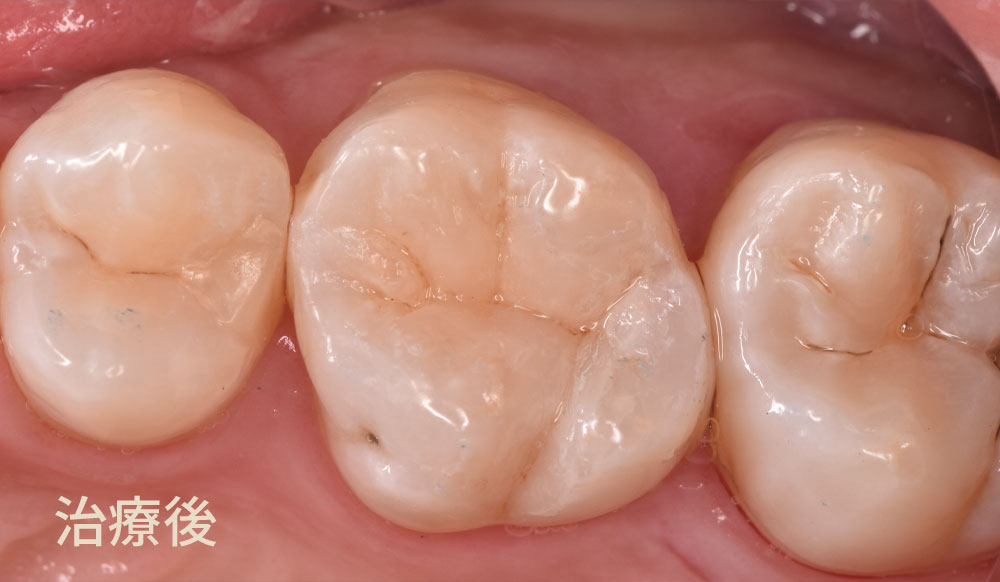

このラバーダム防湿を使用する理由は、お口の唾液などから湿度を減らし接着剤の効能を向上させるために当院では使用しております。ダイレクトボンディング治療は、治療の名称にも使われている直接(ダイレクト)に歯に接着剤を介して高強度の自由診療専用歯科用レジンを接着させる治療方法です。ダイレクトボンド治療にラバーダム防湿を組み合わせることで、接着力が向上し、その結果治療した詰め物が長持ちすることに繋がります。最後に治療後の写真です

治療後の写真はこちらです。奥がダイレクトボディング治療、手前がセラミックインレー治療です。